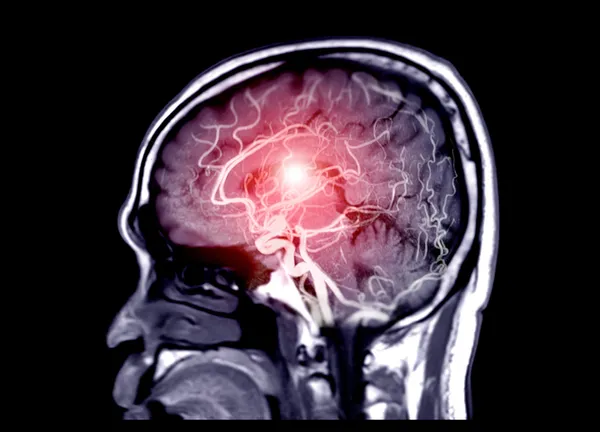

Hastalığın görüntüleme yöntemleriyle açığa çıktığını söyleyen Prof. Dr. Özveren, "Bu hastalığı ultrasonografi, tomografik, anjiyografi, klasik anjiyografi, konvansiyonel anjiyografi yöntemlerle açığa çıkartabiliyoruz. Daralma çok tıkayıcı değilse, klinik sonlanım olmadıysa ya da damarı tıkayan segmentte yüzde 50'den daha az bir daralma söz konusuysa biz bunu ilaç tedavisi ile tedavi edebiliyoruz. İlaç tedavisi bunun küratif olarak olmasını engelleyebiliyor" şeklinde konuştu.